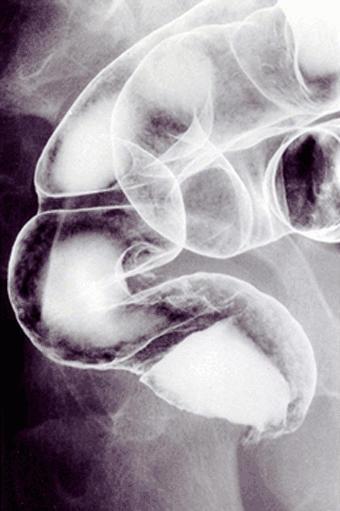

疾病(病理主体)的分类肿瘤样病变/大肠深部囊肿症

部位(按器官分)大肠/直肠

检查方法X线

肿瘤最大直径35~40